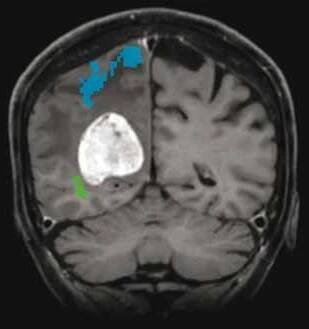

Funkční anatomie a neurologické projevy mozkových metastáz

Mozkové metastázy jsou častou komplikací systémových nádorových onemocnění, z nichž 60–75 % se v průběhu života stává symptomatickými.